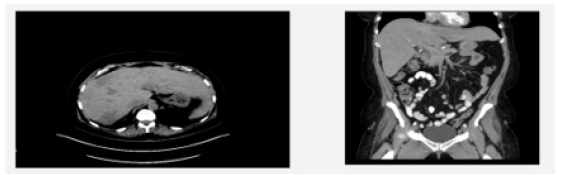

We present a 53-year-old female with diffuse hepatic lesions and widespread lymphadenopathy who was referred to Hepato- pancreato-biliary clinic for evaluation after several failed and inconclusive needle biopsies. She originally presented to her primary care physician for evaluation due to a 4-month history of fevers, chills, drenching night sweats, fatigue, postprandial pain and 40-pound weight loss. Routine labs were unremarkable besides thrombocytosis. CT abdomen and pelvis demonstrated porta hepatis lymphadenopathy and multiple liver lesions (Figure 1). On PET scan she was found to have innumerable masses in the liver and axillary, mediastinal, porta hepatis and retroperitoneal lymphadenopathy with FDG uptake concerning metastatic disease (Figure 2). She was sent to interventional radiology for CT-guided biopsy which revealed necrotizing granulomatous inflammation. Auramine-protamine and AFB staining were negative. She was referred to infectious disease, but extensive workup was negative. Repeat IR biopsy showed fibroinflammatory cells with chronic lymphoplasmacytic and histiocytic inflammation. Given numerous inconclusive results with percutaneous biopsies she was referred to surgery clinic by infectious disease for excisional biopsy. Given her concerning symptoms, lymphoma was also a consideration making surgery a reasonable approach for excisional biopsy with lymphoma protocol. She was seen and evaluated in clinic where we discussed laparoscopic vs an open approach and she elected to undergo an open biopsy. Intraoperatively she was found to have innumerable liver lesions and diffuse porta hepatis lymphadenopathy. Multiple excisional biopsies were obtained from hepatic segments 4, 5, and 6. These were sent for frozen section and permanent. Some of the lesions were sent for microbiology and others sent for cultures, including TB, fungal, anaerobic and aerobic. The hilar lymph nodes were sent for per lymphoma protocol. The frozen section came back as chronic inflammation, non-diagnostic. Permanent biopsies all revealed necrotizing granulomatous inflammation. Cultures were negative for infectious organisms.